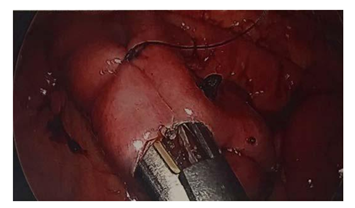

The small bowel lipoma was isolated on the jejunum and observed in active intussusception (Figure 2). The segment of intussuscepted jejunum was resected and re-anastomosed (Figure 3) without complications. The excised specimen was examined extracorporeally (Figure 4) before being sent for tissue evaluation by pathology. The gross specimen was consistent with CT imaging and revealed a 2cm subserosal lipoma. The resected bowel was incised on the back table to reveal an intraluminal lipoma adherent to the jejunal wall without evidence of necrosis or hemorrhage. Pathologic examination confirmed the diagnosis of a homogenous, subserosal lipoma of the jejunum (Figure 5).

Figure 3 Intracorporeal anastomosis of small bowel.